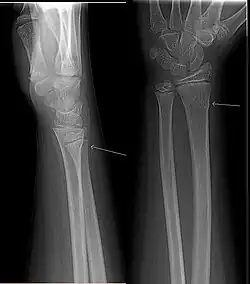

Fracture en bois vert

Une fracture en bois vert est un type de fracture osseuse fréquent chez l'enfant. C'est une fracture située au niveau de la diaphyse de l'os due à une contrainte en hyperflexion. Il s'agit d'une fracture d'une seule corticale avec une rupture du périoste en regard, tandis que le périoste et la corticale du côté de la concavité sont intacts[1]. C'est une fracture stable grâce à la persistance de la charnière périostée, avec néanmoins un risque de déplacement secondaire. C'est une fracture de bon pronostic.